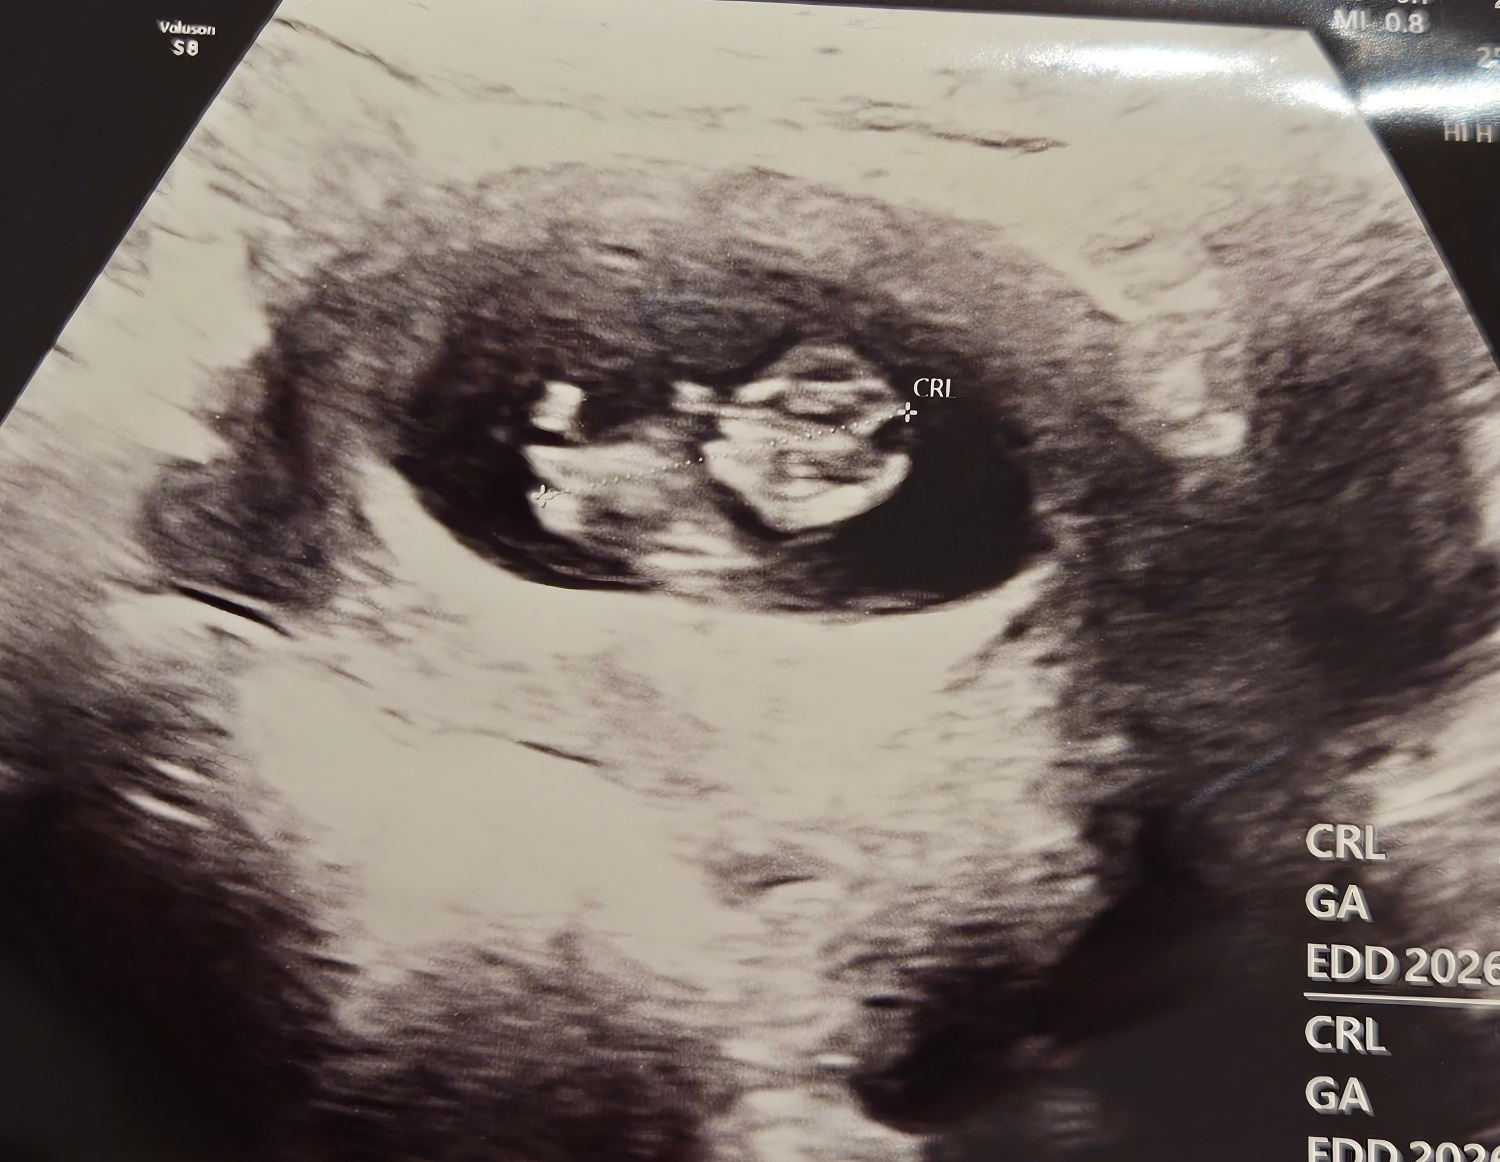

저번주보다 좀더커진젤리곰!

9주5일차에보고온 젤리곰이에요 초음파볼때는 꿈틀꿈틀 거리는것도 보고왔어요 ㅠㅠ너무귀여워요